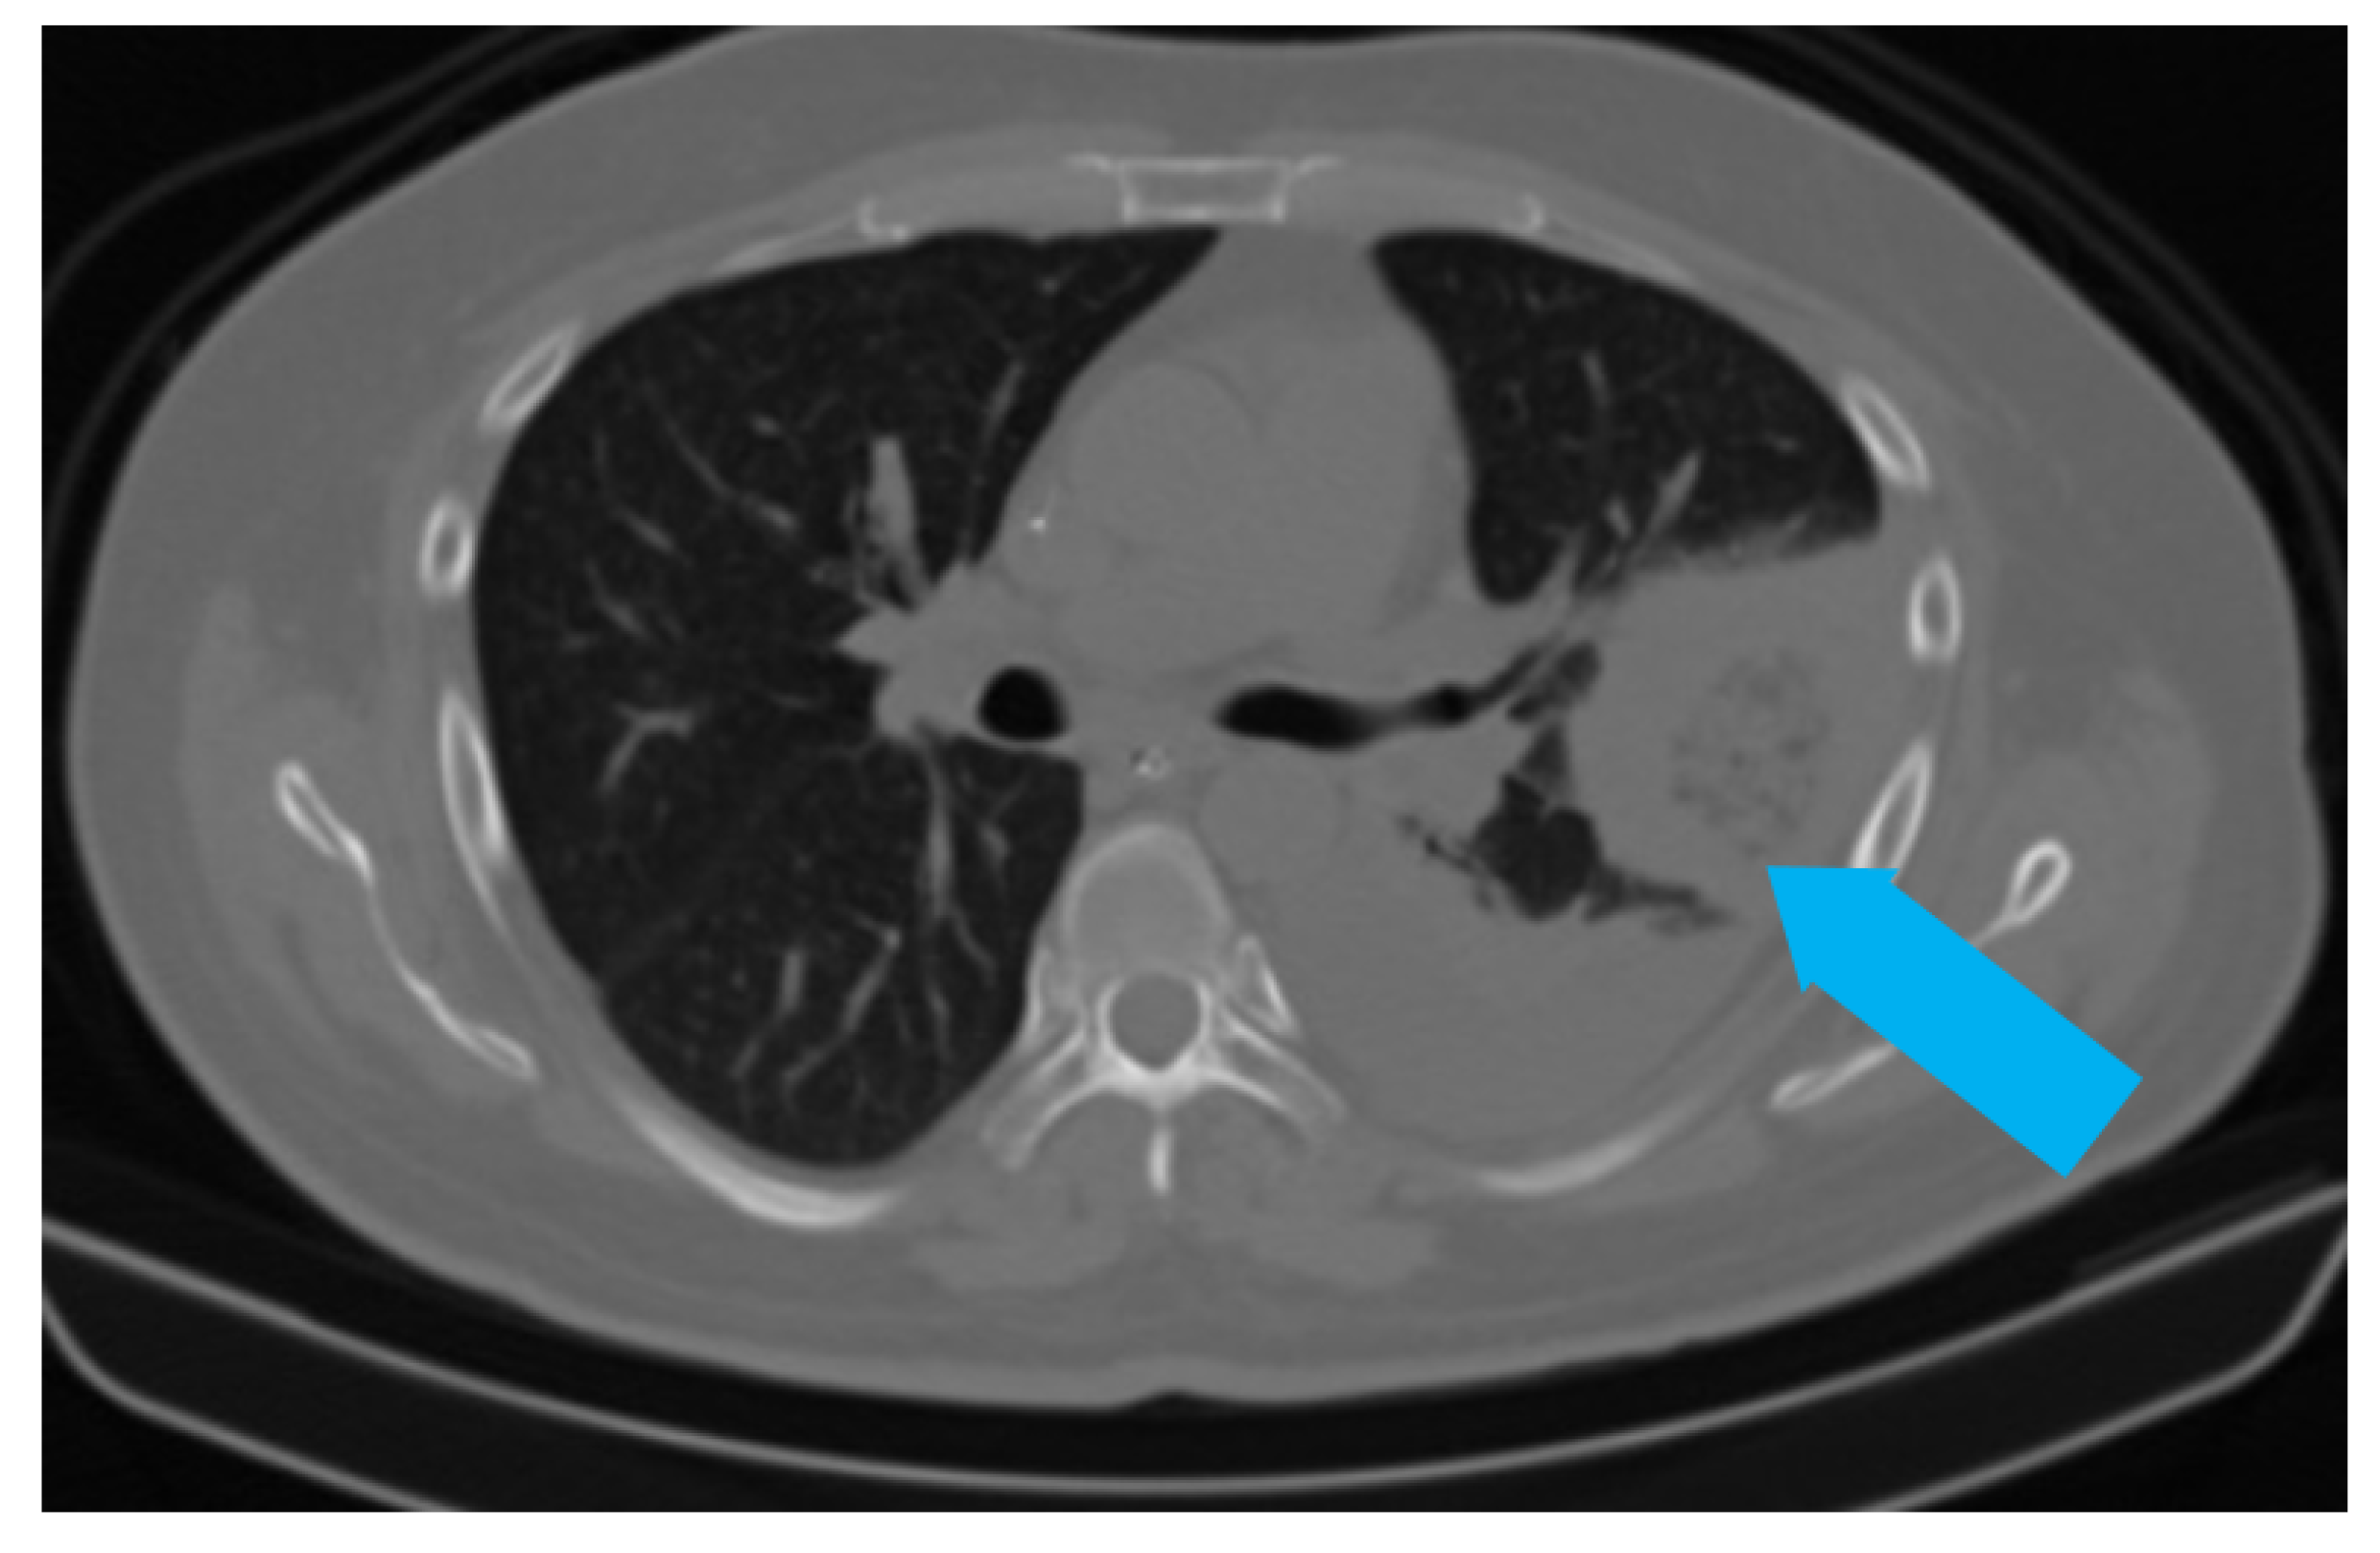

5.1. Role of Diagnostic Imaging

Diagnostic imaging is vital for early detection of invasive mucormycosis in patients with clinical suspicion. Certain distinguishing features of the lung parenchyma on a CT scan of the chest in patients with PM include multiple pulmonary nodules, often pleural-based, presence of lung cavitations and effusions (Figure 1, Figure 2, Figure 3 and Figure 4) [23]. The ‘reverse halo sign’ (central ground glass opacity surrounded by dense consolidation) is highly appreciated, mainly in neutropenic leukemic hosts. In a recent systematic review of CT findings in 16 patients with proven CAPM, consolidation and cavitation were seen in 11 (69%) patients, pleural effusion in 7 (47%), pneumothorax and nodules in 3 (19%) and ‘reverse halo sign’ and pulmonary embolism was seen in 2 (13%) patients [24]. Previously, Nam et al. reported that in hematologic patients, while consolidation and nodules are seen earlier in the disease process, central necrosis, cavitation and the air crescent sign are late findings [25]. This would suggest that CAPM is either under-diagnosed due to lack of differentiation from other fungal, including aspergillosis or bacterial pneumonias, or is diagnosed much later in the illness.

Figure 1. Chest radiograph (AP view) of patient showing round opacity in left lung (blue arrow).

Figure 2. CT scan of the same patient showing a pleural-based consolidation with central clearing (blue arrow) and surrounding, denser, consolidation typical of reverse halo sign; also seen in left mild pleural effusion.